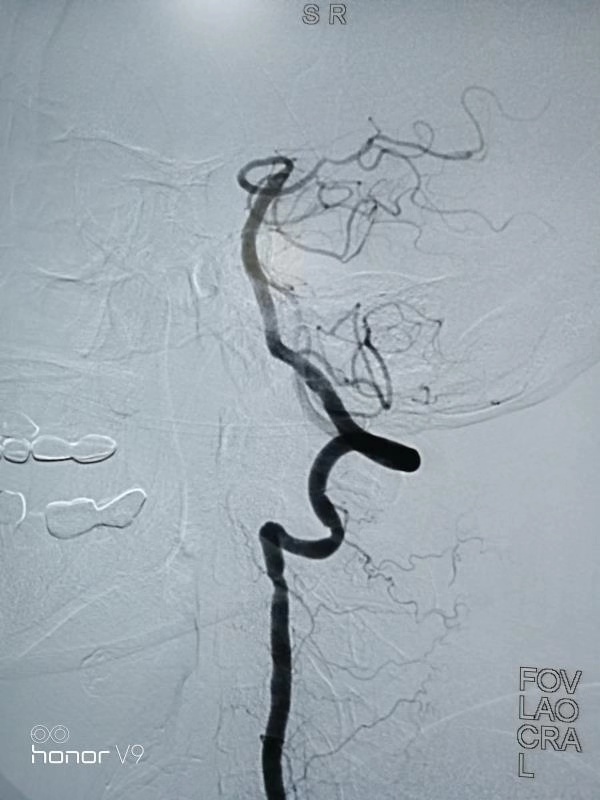

经过努力,医生把动脉里的血栓取出来了!

再造影看,基底动脉血流畅通了(黑色的血流线条连续出现,自下而上由粗到细)。询问王阿婆,她的左边手脚都能抬起来了!